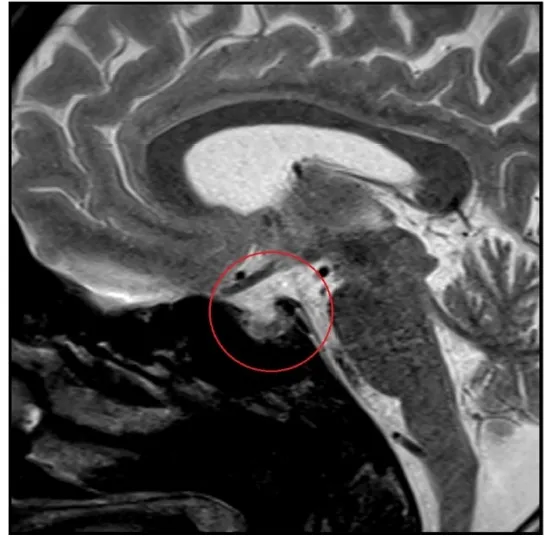

Confere esse caso clínico sobre rebaixamento do sensório e alucinação em paciente dialítico.

Valkercyo Feitosa

3 anos atrás